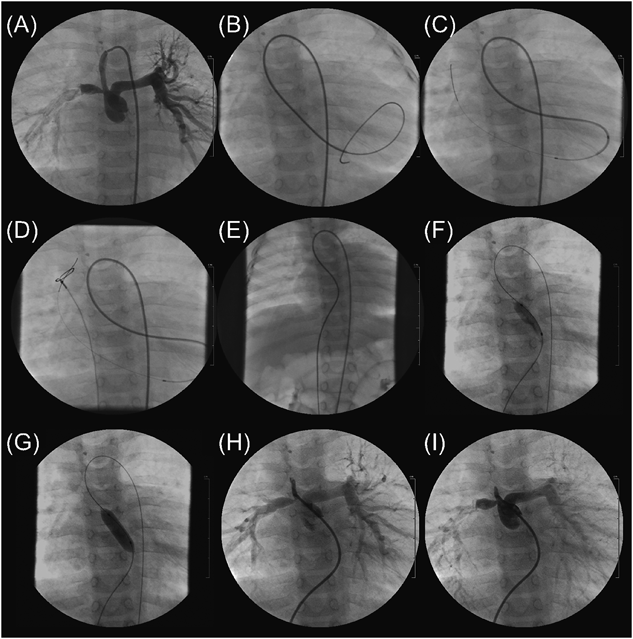

Fig. 2 FA–SPS–FV wire loop to assist BPV in Case 2

(A) A pulmonary arteriogram. (B) From the 4-Fr Judkins right catheter placed into the shunt, a 2.7–2.9-Fr microcatheter following a 0.021″ wire was retrogradely passed through Pin-PV into LV. (C) The tip of the microcatheter was bent upward with a reshaped coronary wire advanced into it, and a 0.016″ guide wire was advanced up into the superior vena cava through MV. (D) The wire was caught with a 10-mm diameter snare catheter advanced via the right FV sheath. (E) The wire was pulled out of the body, and an FA–SPS–FV wire loop was completed. (F) On the wire loop, BPV was performed using a 10 mm diameter×2 cm length balloon catheter.

At 13 months of age, BPV was attempted because his cyanosis deteriorated. Informed consent was obtained from the parents. The diameter of the pulmonary valve was 9.6 mm (Z value, −1.4). A 4-Fr Judkins right coronary artery catheter was advanced into the shunt from which we advanced a 0.021″ wire and a 2.7–2.9-Fr microcatheter (Prograte, Terumo) retrogradely into the LV through the Pin-PV. In the LV apex, the tip of the microcatheter was bent upward with a bent coronary artery wire advancing into it. Next, from the microcatheter, we carefully advanced a 0.016″ GT wire into the SVC through the MV, caught it with a 10-mm diameter snare catheter that was advanced via the right FV sheath, and pulled it out of the body to make an FA–SPS–FV wire loop. Third, we antegradely advanced a 10 mm diameter×2 cm length Sterling balloon catheter into the Pin-PV on the wire loop and performed BPV at 10 atm (Fig. 2). No complications were observed. Following BPV, the pulmonary valve orifice became 3.2 mm, SpO2 rose from 79 to 86%, and Qp/Qs increased from 1.7 to 2.3. Both ventricular sizes were maintained until 30 months of age when he successfully received a Senning and Rastelli procedure.